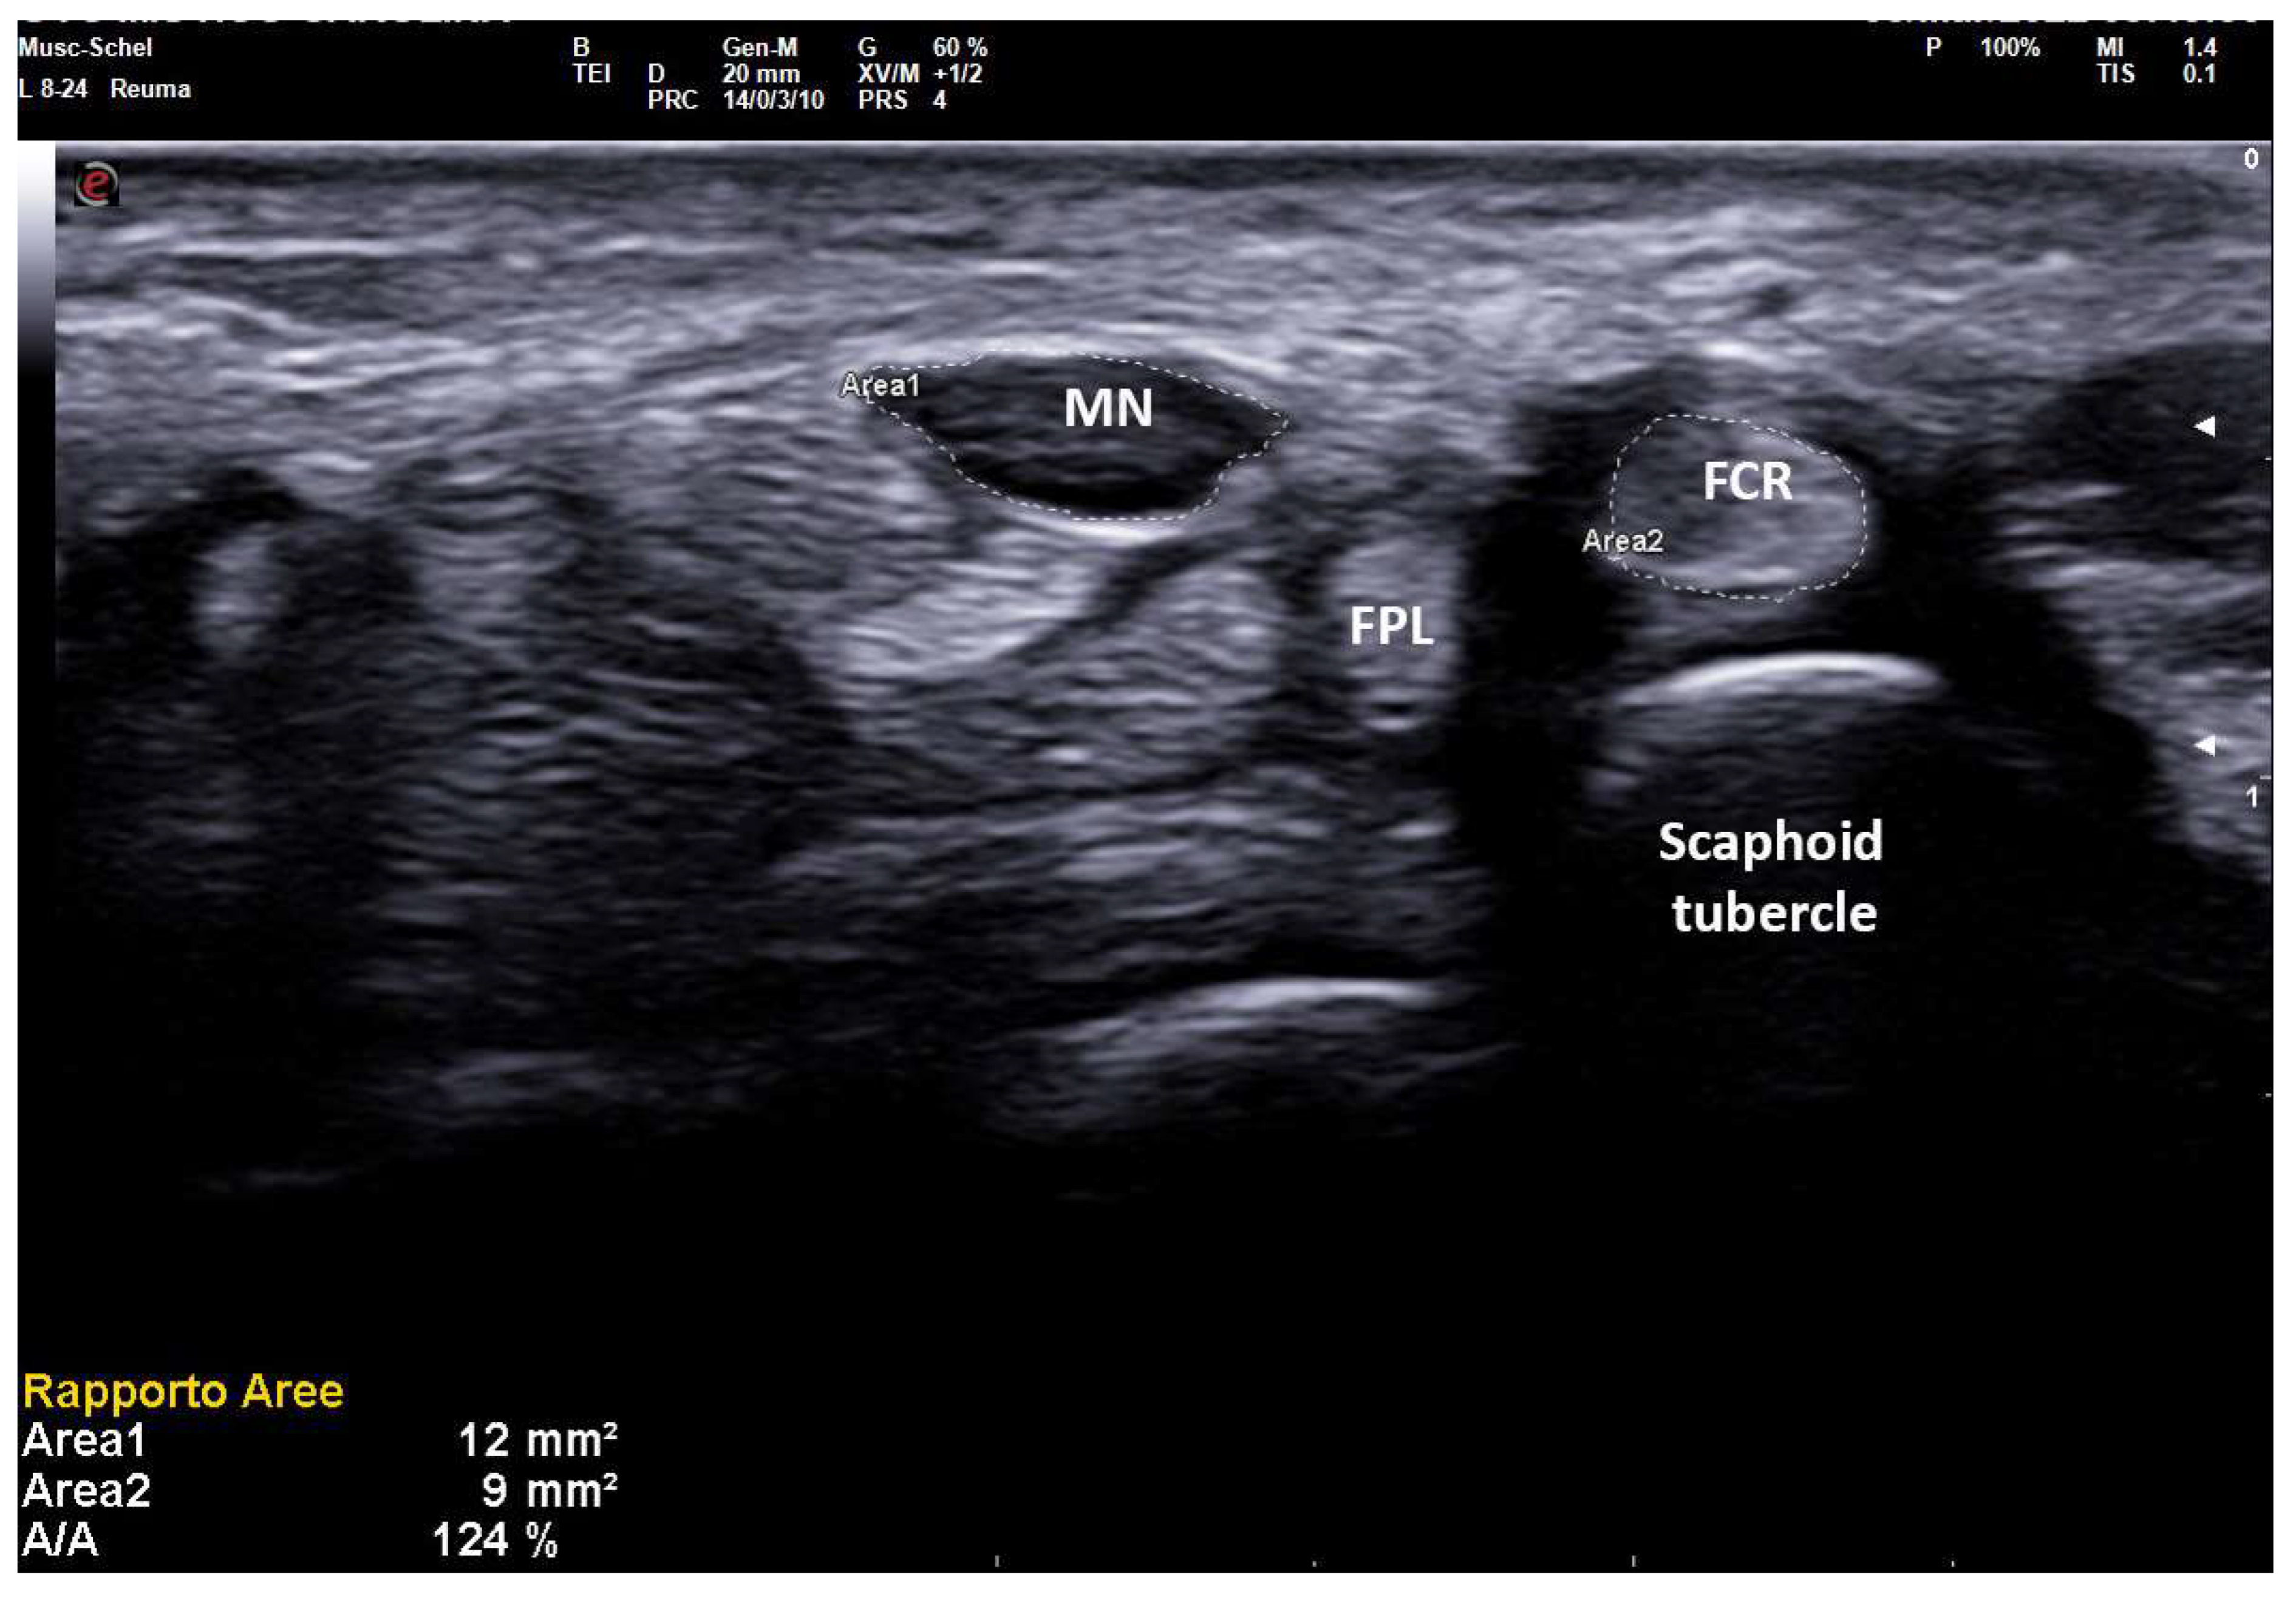

As reported in previous studies [11] MN-CSA is strongly influenced by anthropometric factors in healthy subjects, but in pathologic wrists, the importance of anthropometric parameters is reduced as MN-CSA variability also depends on the severity of neuropathic swelling. Nevertheless, in conditions of anthropometric extremes, large normal nerves or small pathologic nerves could constitute a false positive or false negative in US examination. Even if both crude MN-CSA and NTR showed good correlations with SCV, DML, and finally with PS, in a generic population we demonstrated the superiority of NTR when patients were stratified according to anthropometric extremes. Particularly, in patients taller than 175 cm and shorter than 156 cm, NTR maintained an excellent correlation with PS, while such correlation was lacking for MN-CSA (Figure 5).

Figure 5. Transverse scan over right carpal tunnel in a small female patient (150 cm × 50 kg, 13.7 cm of wrist circumference) affected with medium-grade CTS (Padua Scale 3, SCV 37.1 m/sec, DML 4.8 ms). Linear 8–24 MHz probe. Both areas of median nerve (MN) and flexor carpi radialis (FCR) were manually traced. A MN-CSA of 12 mm2 is not always considered pathologic (cut-off for MN neuropathy until 14–15 mm2 in some studies on CTS) and the severity is often underestimated because of the anthropometric characteristics of the patient. The NTR shows values unequivocally pathologic (124%), as MN-CSA is compared with an anatomic structure (FCR-CSA) that maintains small dimensions in CTS, following the anthropometric characteristics of the patient.